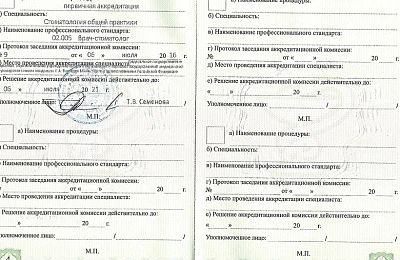

Сертификаты и лицензии

Образование

Пермская государственная медицинская академия им. акад. Е.А. Вагнера (стоматология), базовое образование